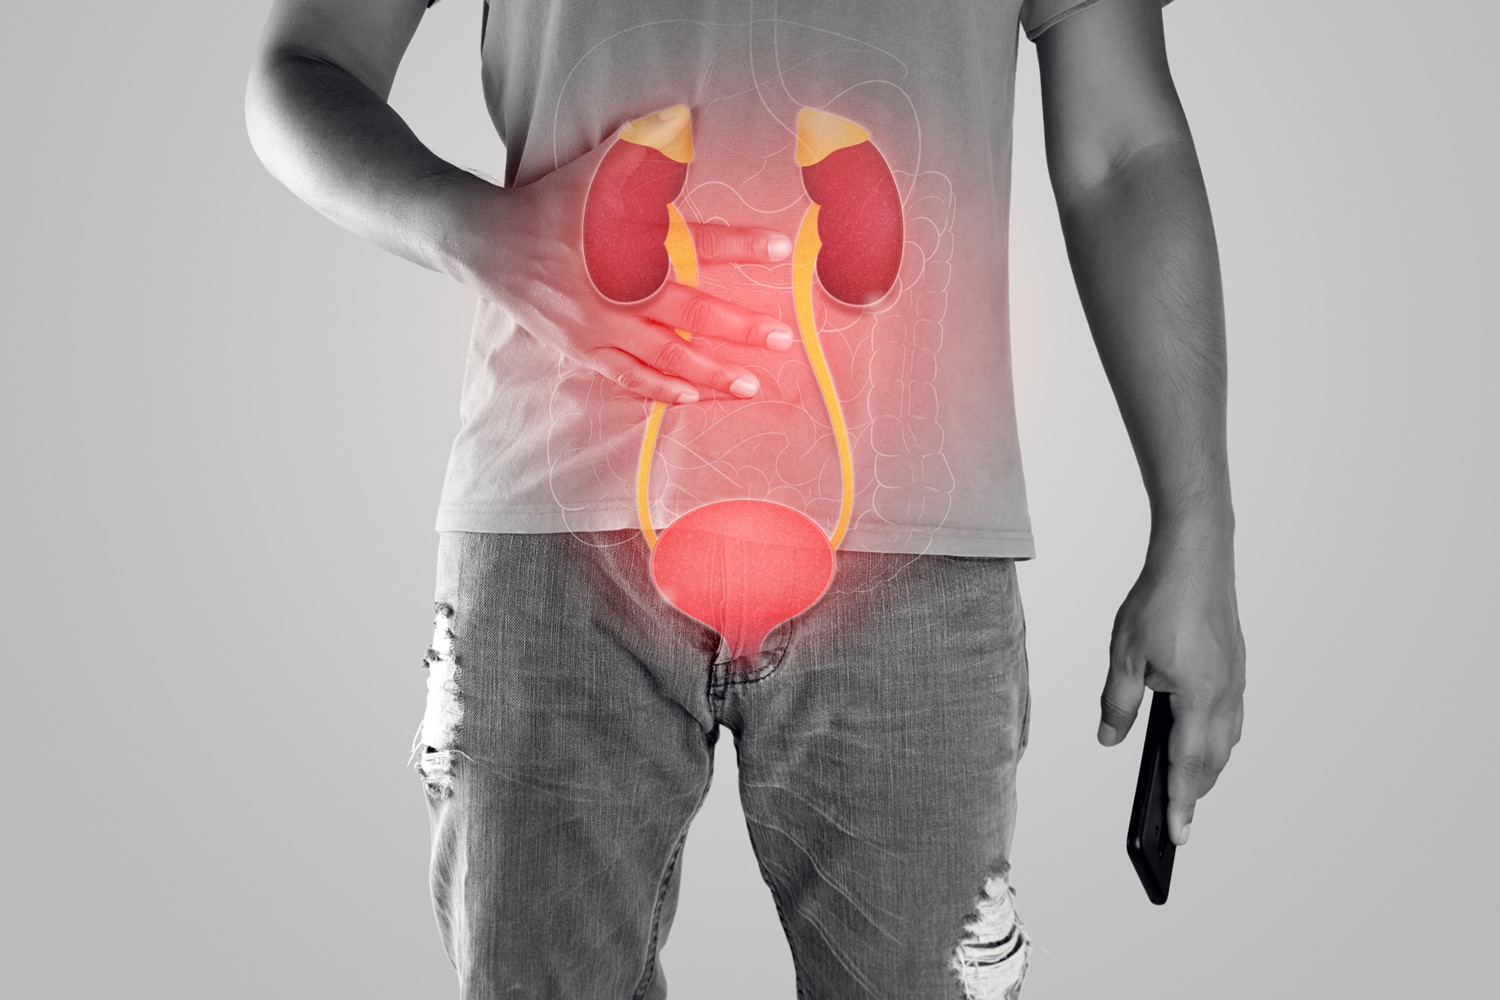

Urinary tract infections (UTIs) are a common health problem, affecting millions of people every year. While most UTIs are acute

A chronic or persistent urinary tract infection is an ongoing infection of the urinary tract for a prolonged period despite

Chronic Kidney Disease (CKD) is a condition that affects the function of the kidneys. This disease can lead to kidney

Chronic Kidney Disease (CKD) is a condition that affects millions of people worldwide. It is often referred to as a

Chronic Kidney Disease (CKD), also known as chronic kidney failure, is a condition characterized by the gradual loss of kidney